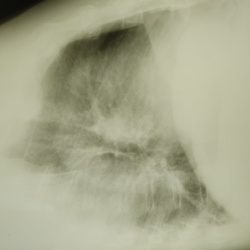

Здравствуйте, мужчина 64 года, неделю назад выставили левостороннюю нижнедолевую пневмонию. На данный момент клиника ушла. Прошлых снимков нет. В s9-10 это пневмо фиброз?